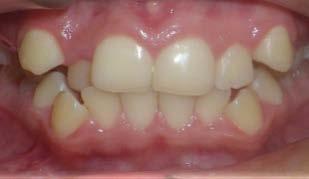

Paciente femenina de 15 años de edad que acudió a la Clínica de Ortodoncia Instituto Profesional Odontológico Contemporáneo (IPOC) en Saltillo, Coahuila, México. El motivo de su consulta fue que “quiero brackets porque sus colmillos están encimados”. Los estudios de rutina le fueron solicitados en la historia clínica SDCP. A la inspección clínica se observó paciente mesofacial, forma facial ovalada, con lado de compresión del lado derecho y lado de distracción del lado izquierdo, perfil recto, línea media facial y dental inferior no coincidían, tercio inferior aumentado, labios medianos e incompetencia labial (Figura 1).

El examen clínico intraoral reveló una clase I molar bilateral, caninos superiores en infraoclusión, por ende la clase canina no se puede clasificar, presencia de apiñamiento severo, rotaciones en premolares superiores e inferiores, línea media inferior desviada hacia el lado derecho 3.5 mm,

Figura 1. Paciente femenina 15 años de edad.

falta de coordinación de las arcadas, el arco inferior con forma cuadrada y el superior forma ovoide, el overjet de 2 mm y el overbite de 2 mm (Figura 2).

Figura 2. Fotografías intraorales iniciales.